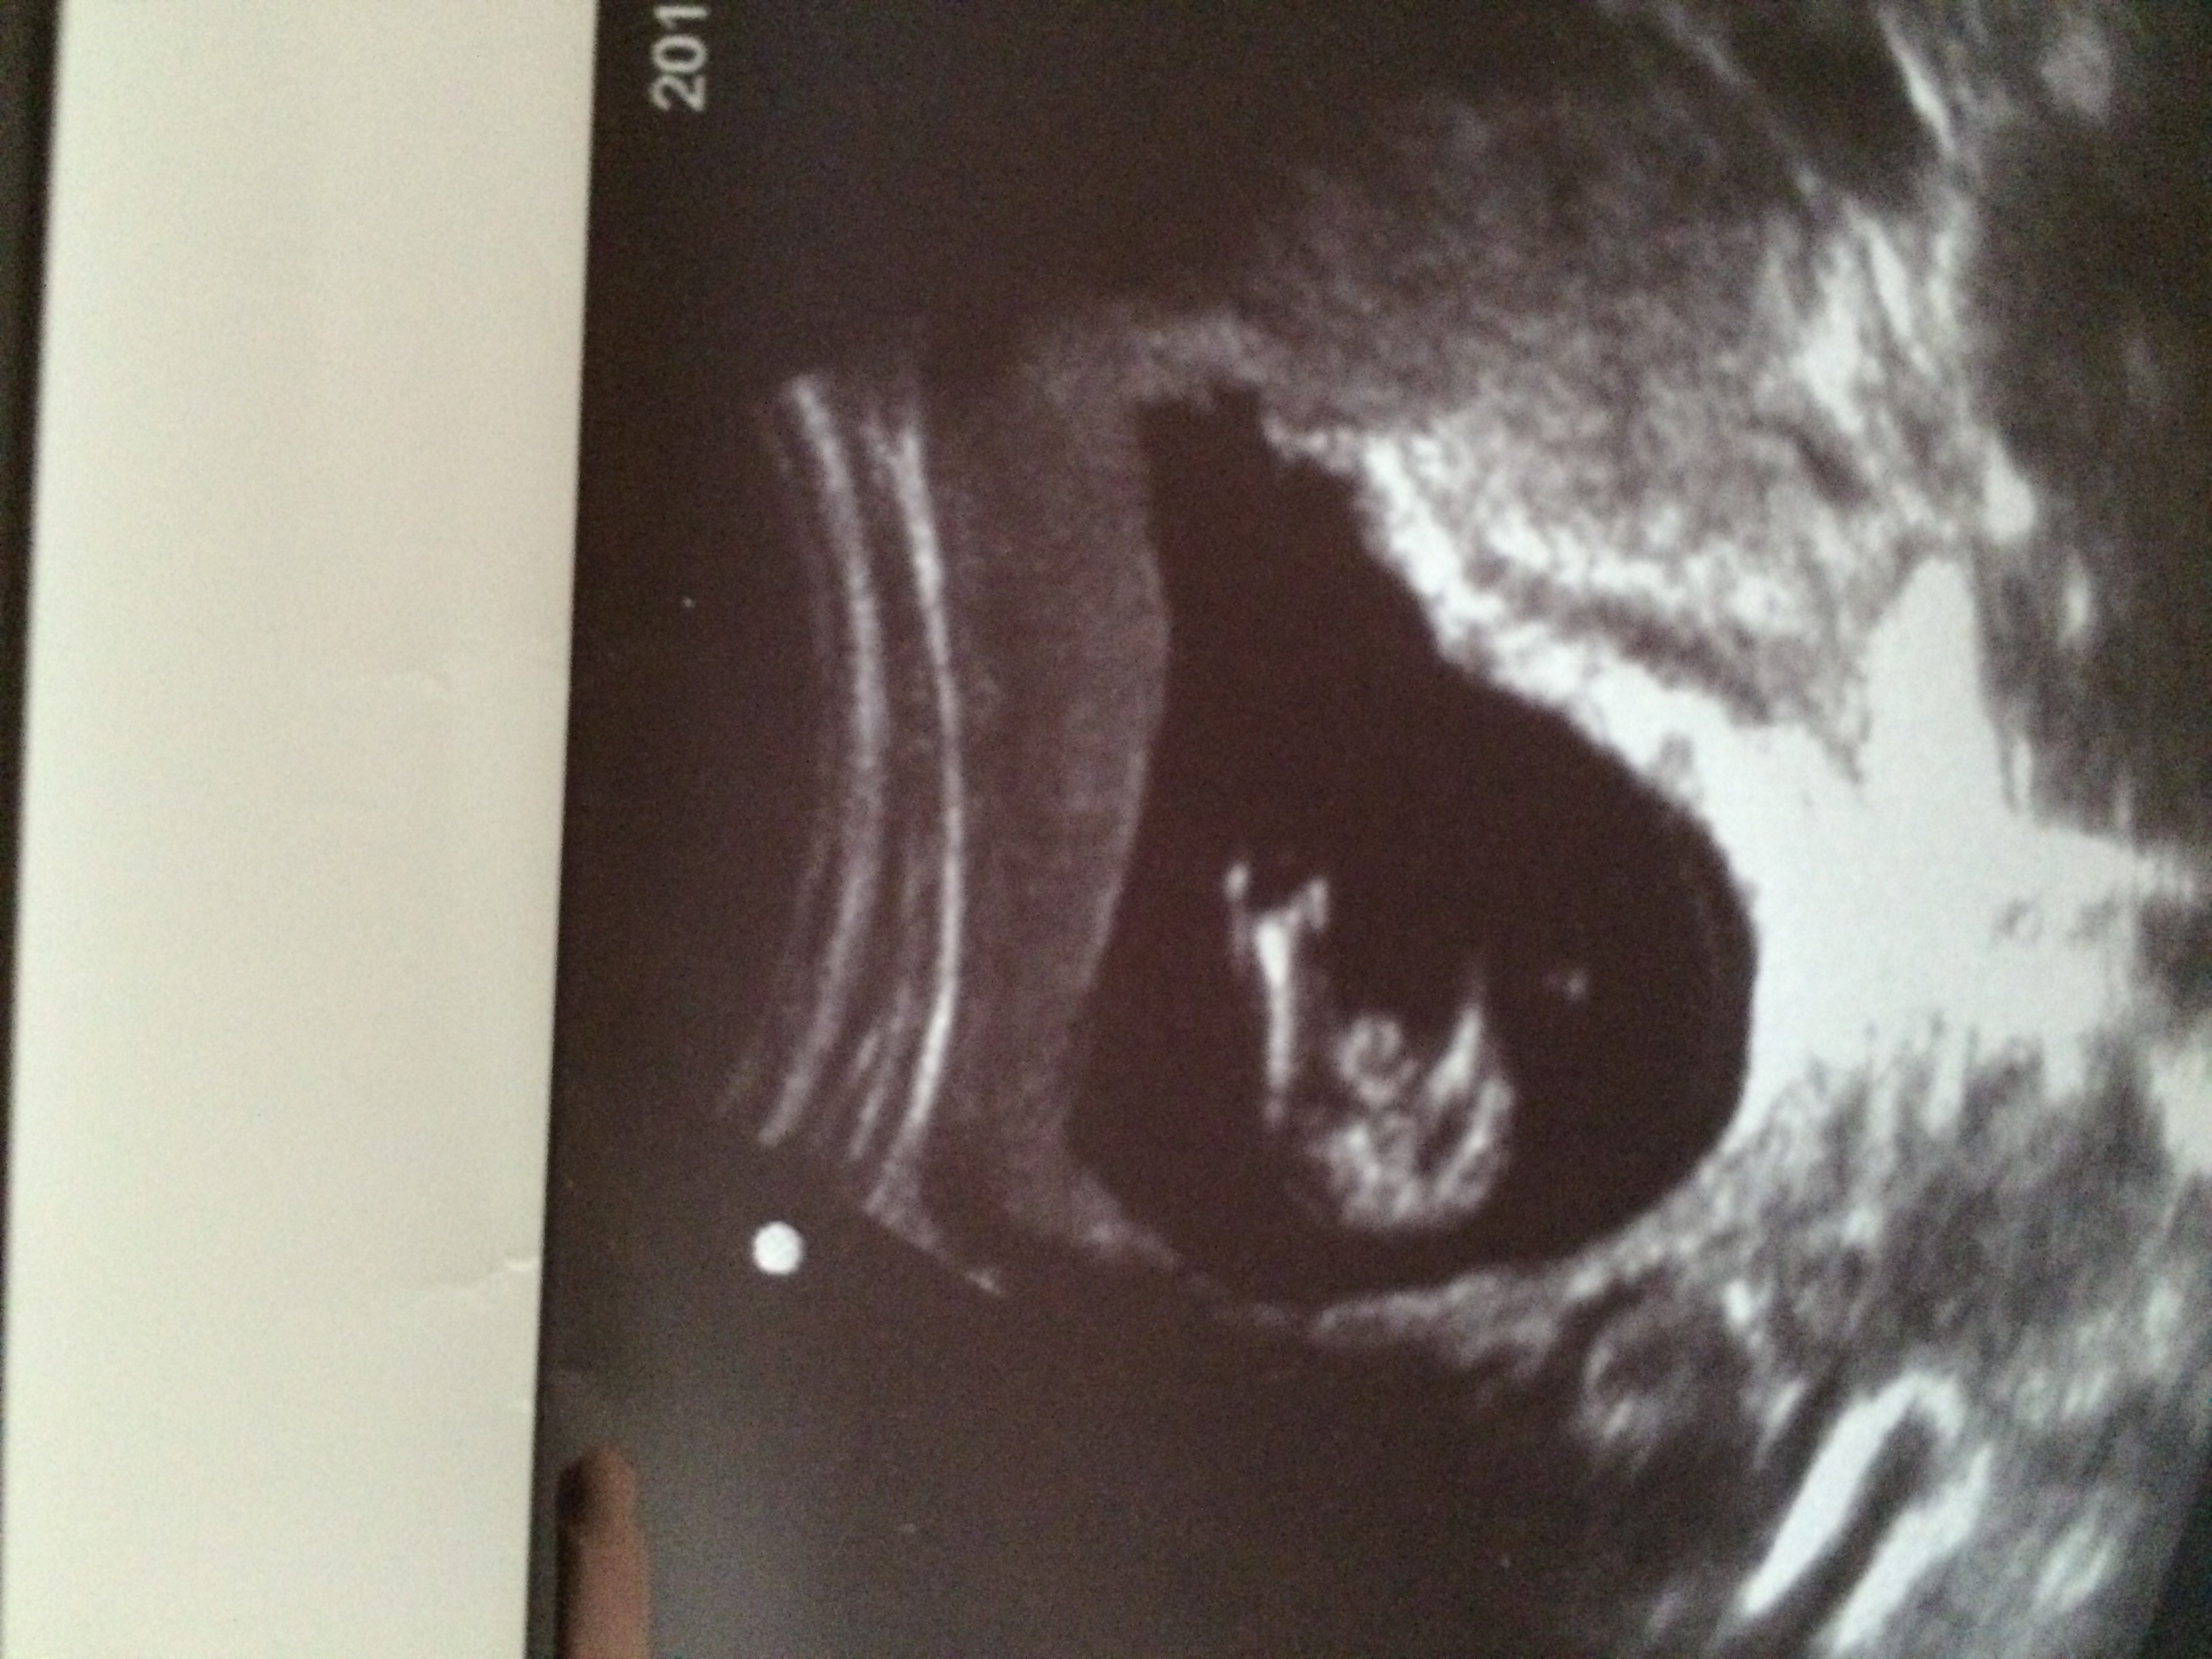

Doctor said boy but I just can't tell! Obvious protrusion and no hamburger appearance. I do not have a profile shot.